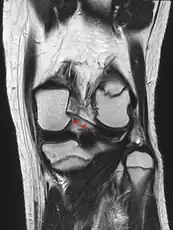

Posterior meniscofemoral ligament on MRI, sagittal

Posterior meniscofemoral ligament (Wrisberg) behind the posterior horn of the lateral meniscus close to its insertion. Sometimes wrongly interpreted as a meniscal tear.